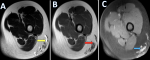

A 12-year-old female presented to the dermatology department with a history of gradually progressive swelling over the posterolateral aspect of the left thigh for the past six months. The overlying skin appeared normal without discoloration or ulceration. Neurovascular examination of the limb was normal. Contrast-enhanced magnetic resonance imaging (MRI) of the left thigh revealed multiple, well-defined cystic lesions within the subcutaneous plane of the posterolateral aspect of the left thigh. These lesions appeared hyperintense on T2 and T2 fat-suppressed sequences, hypointense on T1, and showed minimal thin peripheral enhancement following contrast administration. No diffusion restriction on DWI images. The underlying muscles, myofascial planes, femoral cortex, and neurovascular bundles were intact. The lesions collectively measured approximately 2.2 x 2.6 x 3 cm (AP X TR X CC). Ultrasonography was done for correlation of the left thigh, which shows a well-defined, multiloculated cystic lesion confined to the subcutaneous plane. The lesion showed multiple thin internal septations with anechoic contents and no significant internal vascularity on Doppler. Based on the combined radiological findings, the final diagnosis of lymphangioma circumscriptum of the left thigh was made. The patient was referred to pediatric surgery for further evaluation. Surgical excision was planned due to progressive enlargement and cosmetic concerns. Complete excision of the superficial lesion was performed. Histopathological examination confirmed the diagnosis of lymphangioma circumscriptum of the left thigh. The postoperative period was uneventful. At short-term follow-up (3months), there was satisfactory wound healing with no evidence of recurrence.

Figure 1: axial magnetic resonance imaging images of the left thigh demonstrating multiple well-defined cystic lesions in the subcutaneous plane of the posterolateral aspect of the thigh (arrows); A) T2-weighted image showing hyperintense cystic lesions (yellow arrow) in the subcutaneous tissue; B) T1-weighted image demonstrating hypointense signal intensity of the same lesions (red arrow); C) Post-contrast T1 fat-suppressed image showing minimal thin peripheral enhancement of the cystic lesions (blue arrow)